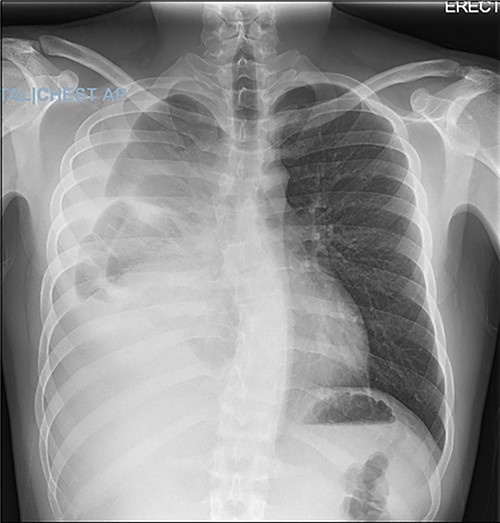

A 22-year-old male patient with no significant medical or surgical history and no smoking history presented to the emergency department for evaluation of persistent cough for 3 weeks. The cough was initially associated with chest pain, which then subsided. He denied fever, chills, nasal congestion, shortness of breath and sore throat. A viral panel including COVID-19 was negative and patient was vaccinated against COVID-19. Chest X-ray (Fig. 1) demonstrated a large right pleural effusion with right lower lung consolidation. To further investigate the chest X-ray findings, a computed tomography (CT) of the thorax (Fig. 2) was performed, revealing a 17.2 cm mass occupying the right hemithorax causing a leftward mediastinal shift and narrowing of the right-sided bronchi. To better determine the etiology of the mass, a biopsy was obtained via CT-guided fine needle aspiration. Although analysis of this specimen exhibited mostly necrotic material, it also showed nests of monomorphic epithelial-like cells with many small mature lymphocytes and findings consistent with a thymic neoplasm. Germ cell tumor markers were negative. The beta-hCG, AFP and LDH markers were also negative. However, a more definitive diagnosis was unable to be determined due to the scant amount of collected specimen. Given the clinical, radiographic and pathologic findings, the patient was scheduled for resection of the mass.